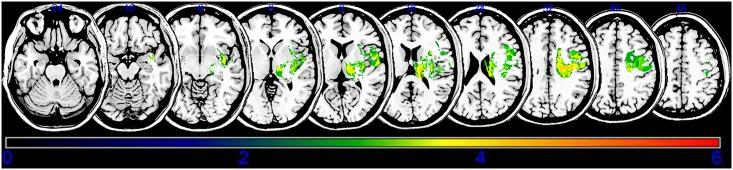

Spasticity is an important barrier that can hinder the restoration of function in stroke patients. Although several studies have attempted to elucidate the relationship between brain lesions and spasticity, the effects of specific brain lesions on the development of spasticity remain unclear. Thus, the present study investigated the effects of stroke lesions on spasticity in stroke patients. The present retrospective longitudinal observational study assessed 45 stroke patients using the modified Ashworth Scale to measure muscle spasticity. Each patient was assessed four times: initially (within 2 weeks of stroke) and at 1, 3, and 6 months after the onset of stroke. Brain lesions were analyzed using voxel-based lesion symptom mapping (VLSM) with magnetic resonance imaging images. Spasticity developed to a certain degree within 3 months in most stroke patients with spasticity. The VLSM method with non-parametric mapping revealed that lesions in the superior corona radiata, posterior limb of the internal capsule, posterior corona radiata, thalamus, putamen, premotor cortex, and insula were associated with the development of upper-limb spasticity. Additionally, lesions of the superior corona radiata, posterior limb of the internal capsule, caudate nucleus, posterior corona radiata, thalamus, putamen, and external capsule were associated with the development of lower-limb spasticity. The present study identified several brain lesions that contributed to post-stroke spasticity. Specifically, the involvement of white matter tracts and the striatum influenced the development of spasticity in the upper and lower limbs of stroke patients. These results may be useful for planning rehabilitation strategies and for understanding the pathophysiology of spasticity in stroke patients.

痉挛是阻碍脑卒中患者功能恢复的重要障碍。尽管已有多项研究试图阐明脑损伤与痉挛之间的关系,但特定脑损伤对痉挛发展的影响仍不清楚。因此,本研究旨在探讨脑卒中患者脑损伤与痉挛的关系。本回顾性纵向观察研究使用改良 Ashworth 量表评估了 45 例脑卒中患者的肌肉痉挛程度。每位患者评估 4 次:脑卒中后 2 周内首次评估,然后分别在 1、3 和 6 个月时进行评估。采用磁共振成像图像的基于体素的病变症状映射(VLSM)分析脑损伤。大多数痉挛性脑卒中患者在 3 个月内痉挛发展到一定程度。非参数映射的 VLSM 方法显示,上放射冠、内囊后肢、后放射冠、丘脑、壳核、运动前皮质和岛叶的病变与上肢痉挛的发展有关。此外,上放射冠、内囊后肢、尾状核、后放射冠、丘脑、壳核和外囊的病变与下肢痉挛的发展有关。本研究确定了几个导致脑卒中后痉挛的脑损伤。具体来说,白质束和纹状体的参与影响了脑卒中患者上下肢痉挛的发展。这些结果可能有助于制定康复策略,并有助于理解脑卒中患者痉挛的病理生理学。